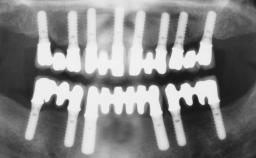

Conventional Loading of Six Implants in the Mandible and Final Restoration with a Full-Arch Metal-Ceramic FDP

A 68-year-old, completely edentulous male patient presented for evaluation and treatment options. He reported excellent general health and was taking no regular medication. He had been edentulous for approximately 12 years, having lost his teeth to periodontal disease and dental caries. The patient’s chief complaint was incompetent function. His secondary concerns included his appearance and the desire for a predictable outcome. He attributed his reduced functional capacity to his lower complete denture, which he described as poor. He was particularly concerned with the denture’s instability and poor fit. In general terms, he was satisfied with the maxillary complete prosthesis. The maxillary prosthesis was characterized by adequate retention, stability, and support, although the fit was considered less than ideal.

# of Implants 6

Type of Implants One-Piece

Prosthesis Type FDP

Surgical SAC classification

SAC Level Advanced

Defining Characteristics Fully edentulous lower jaw to be rehabilitated with two or more implants

Modality > 4 implants, extending to mental nerve region

Bone Volume Horizontally and vertically sufficient